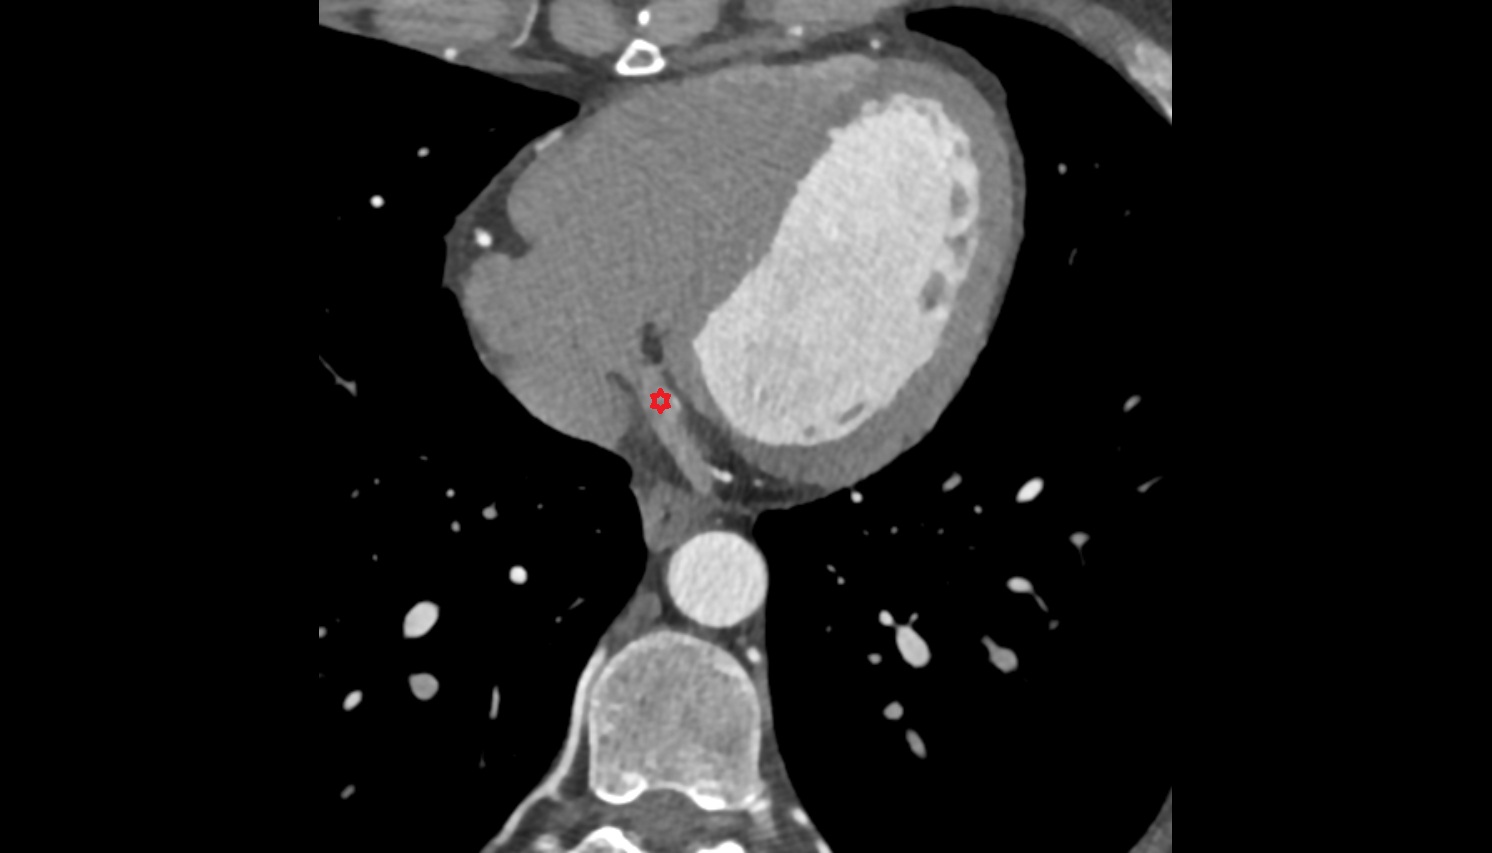

- Heart

- Left ventricle

- Right atrium

- Left atrium

- Right ventricle

- Aortic root

- Ascending aorta